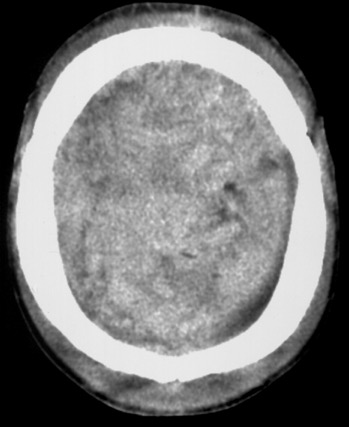

HED vertex